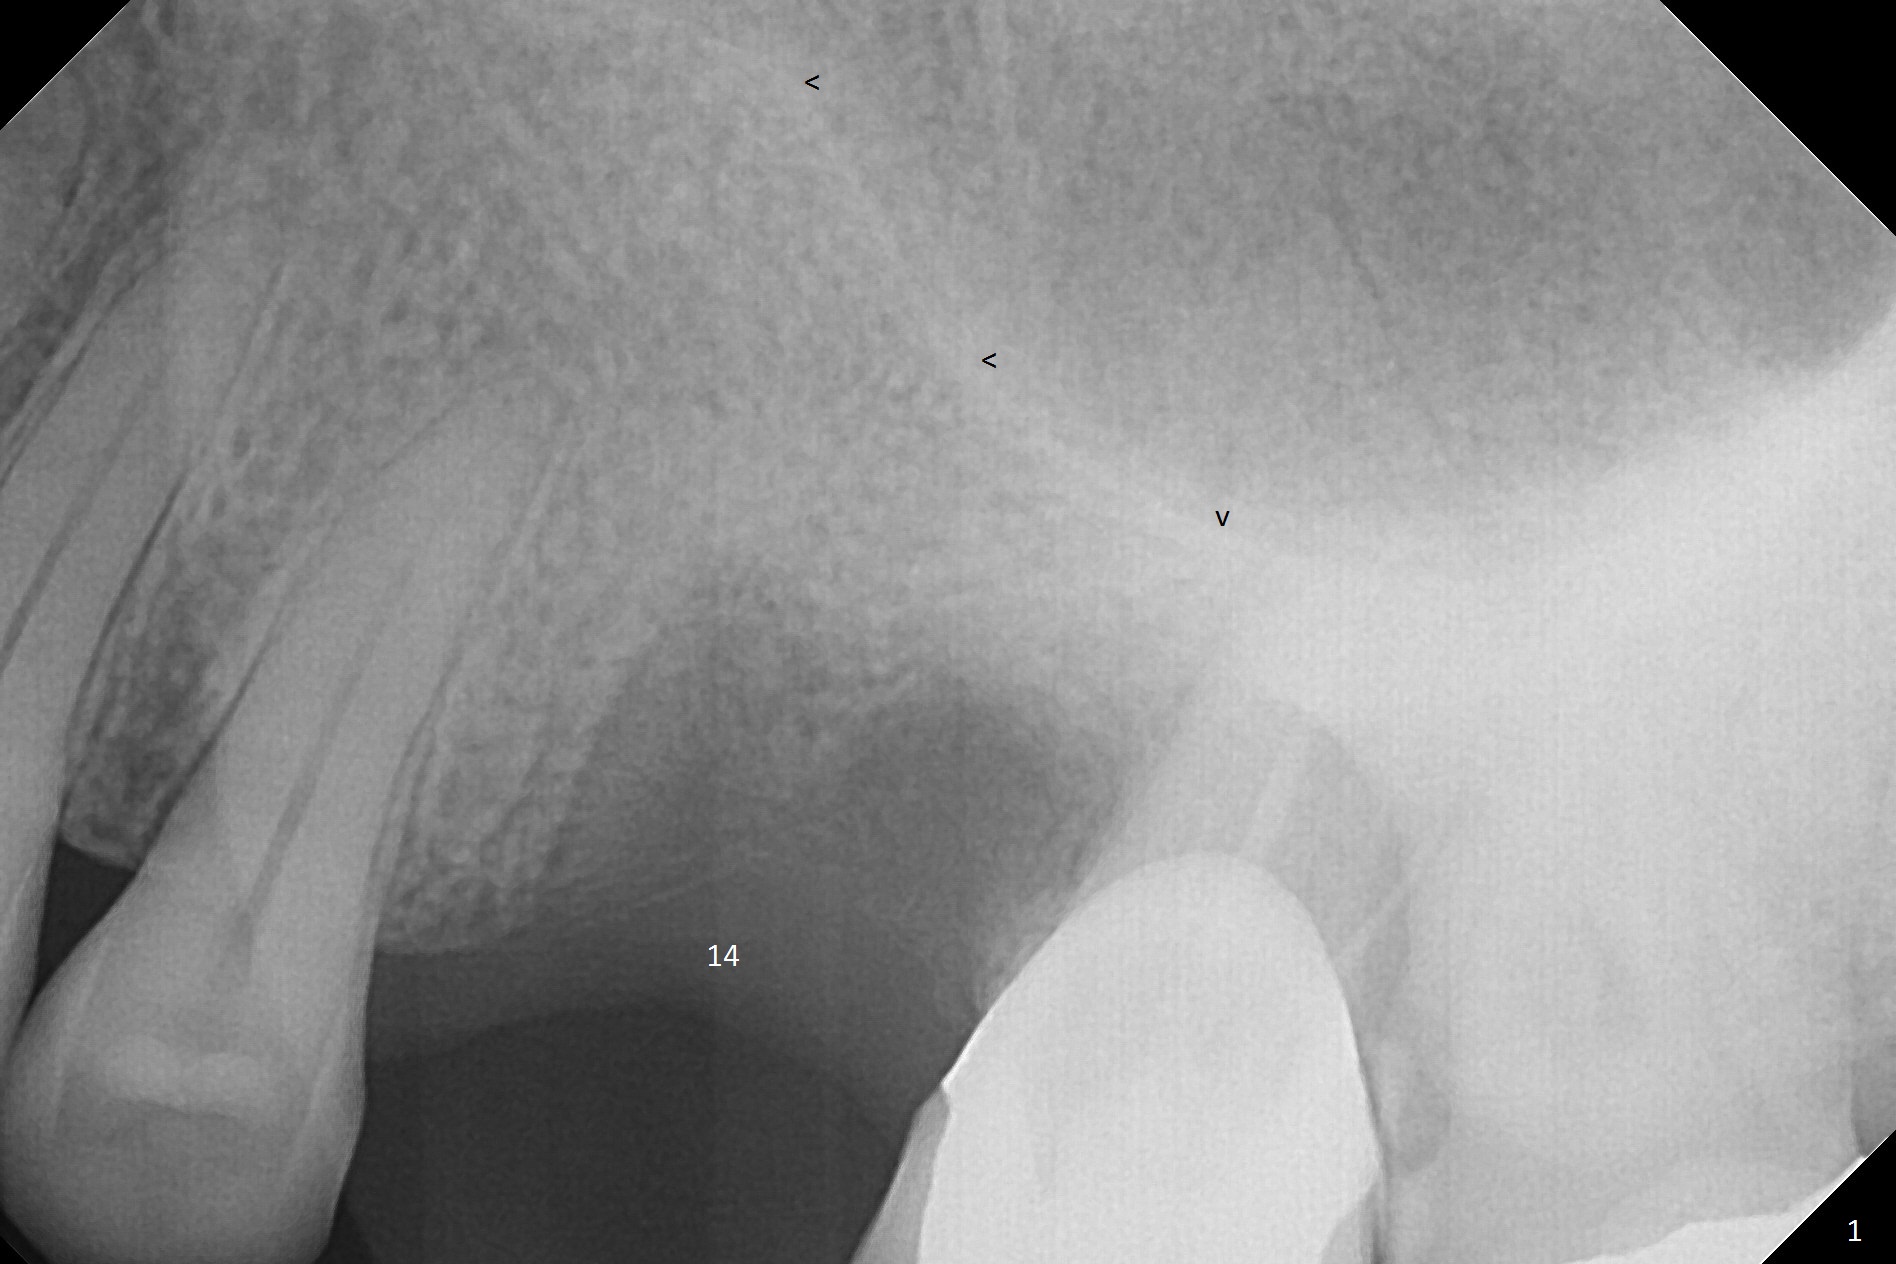

Low Density Post Extraction

A 44-year-old woman will return to clinic for #14 implant placement 2.5 months post extraction (Fig.1). The tooth used to have persistent fistula. The bone density appears to be low coronally. To compensate for the sloped sinus floor (arrowheads), start osteotomy as mesial as possible (Fig.2 red arrow) either with Magic Expander or Drill and place an implant as high as possible (Fig.3). If there is buccal plate defect, place the implant as palatal and deep as possible. Use Metronidazole routinely for sinus cases.